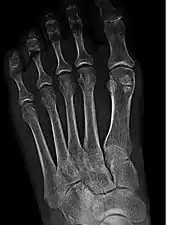

Sesamoid bones at the distal end of the first metatarsal bone of the foot.